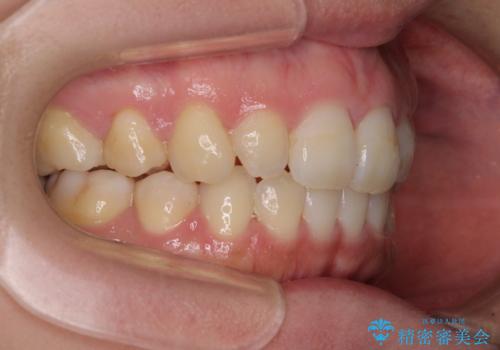

インビザラインによる矯正治療は、どれだけマウスピースを外す時間を短くできるかが成功の鍵となりますが、抜歯矯正ではよりシビアに要求されます。

こちらの患者様は、1日22時間以上を厳守してくださり、3年強で終えることができました。